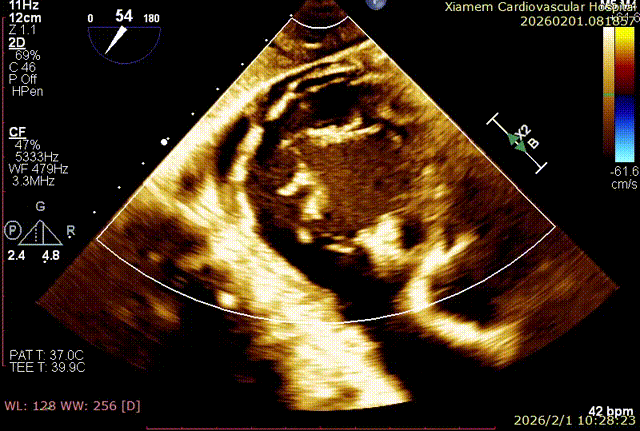

第一个夹子释放后,在前叶、隔叶间靠近中央区仍有残余反流,所以决定再植入一枚 6mm 夹合器。第二枚夹合器抓捕瓣叶过程中,受到第一枚夹合器影响,无法清晰的在 X-plane 切面上进行瓣叶捕获,因此改用 3D-MultiView 切面顺利抓捕,关闭夹合器后残余反流已经由术前极重度(4+)减小为轻中度(2+),手术过程流畅,手术结果完美。

术后即刻反流改善为2+